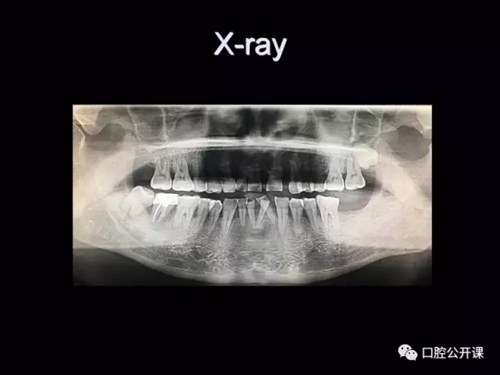

一例廣泛型侵襲性牙周炎5年臨床追蹤下

楊淑銀醫(yī)師用他的一例侵襲性牙周炎五年臨床病例追蹤來縮影一個青年牙周醫(yī)師的成長之路,帶我們一起探索看似平凡枯燥的牙周基礎治療到底有怎樣的重要性?